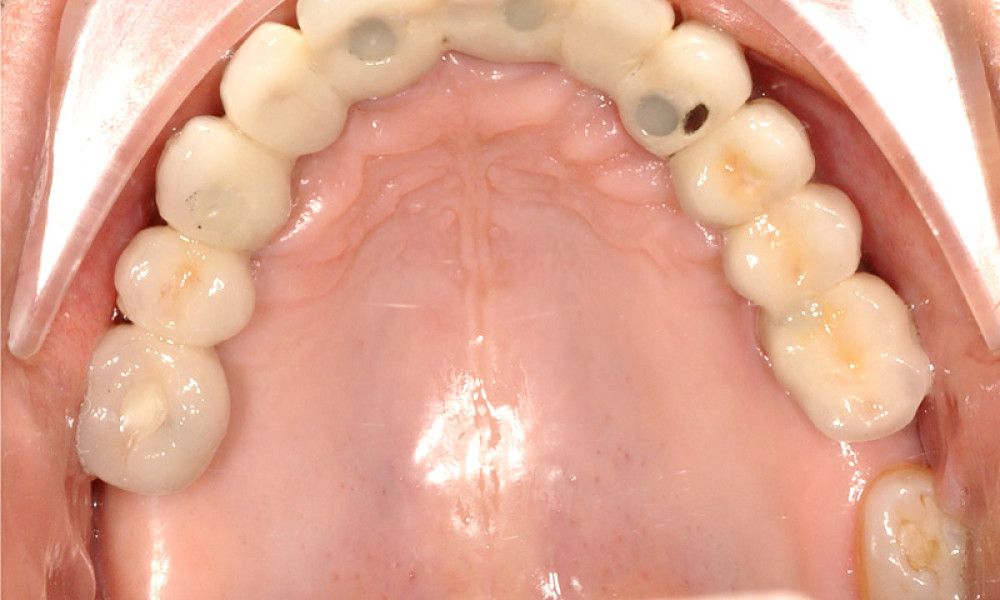

Los Implantes de Carga Inmediata son una solución práctica y definitiva para el desdentado total, es un tratamiento el cual una vez que se opera y se colocan los implantes, por un periodo entre 24 horas a 48 horas, se colocan los dientes en forma provisional, de esta forma el paciente queda con algo fijo mientras el implante se adhiere al hueso. Su principal ventaja radica en la reducción o eliminación del tiempo de espera entre la colocación del implante dental y la colocación de los dientes fijos.

Son recomendables para personas que no están dispuestas a una prótesis removible y quienes quieren acortar los tiempos de espera.